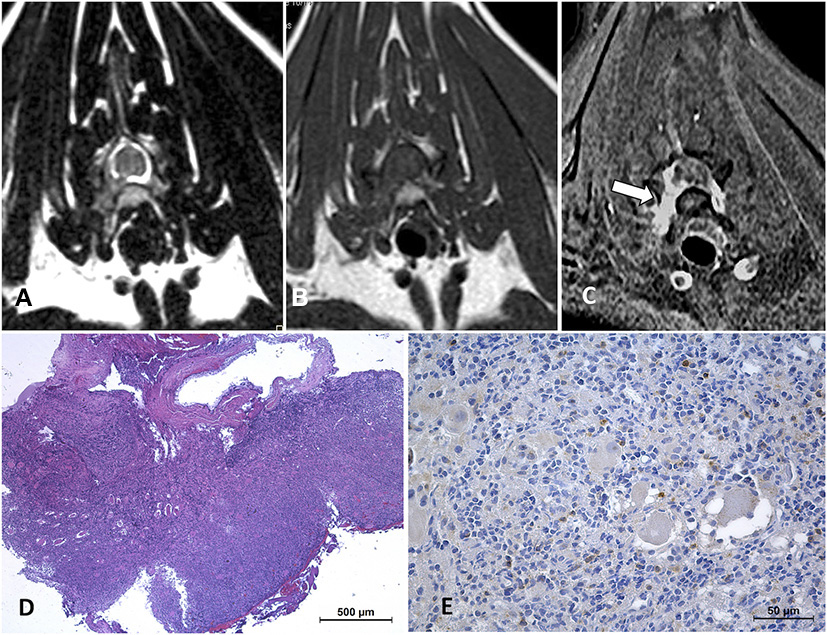

Lesions involving nerve roots and causing spinal cord compression were present in 5/27 (18.5%) cases, localized in the right C5 to C8 nerve roots, the right C6-C7 nerve roots (Figure 2), bilateral L5-L7 nerve roots 1/5, right L6 and left L7, and bilateral L5-S3 (Figure 3), respectively. An intramedullary lesion located at C4-C5 and a separate lesion involving the right C6-C7-C8 nerve roots was observed in 1/27 (3.7%) cases.

Figure 2

Cervical neurolymphomatosis in a 2.5-year-old domestic short-haired cat which presented with a 3-month-course of right thoracic limb lameness progressing to monoparesis. In the MRI transverse planes at the level of C6-C7 intervertebral foramina, there is a diffuse enlargement of the right C7 spinal nerve and root with mild spinal cord contralateral displacement (arrows on A–C). The lesion is iso-hyperintense on T2W images (A), isointense on T1W (B), and enhances with an intense and heterogeneous pattern on post-contrast SPIR images (C). On biopsy tissue (D) neoplastic lymphoid cells are infiltrating adjacent tissues, HE. CD 20-immune positive cells predominate in the neoplastic lymphoid cell population (E). The final diagnosis was neural and ganglionar small non-cleaved B-cell lymphoma.

Dorsal STIR (A) and transverse T1W pre- (B) and T1W post-contrast (C) images of the lumbar vertebral column of an 11-year-old Turkish Van cat with progressive non-ambulatory paraparesis. There is bilateral diffuse nerve root enlargement (arrows), which shows hyperintense on STIR (A), mildly hyperintense on T1W (B) and heterogeneously enhancing (C). A surgical biopsy smear (D) showed an abnormal population of pleomorphic lymphoid cells, with immature large lymphocytes with more abundant cytoplasm and pale chromatin (arrows), Romanowsky, 100x. Intraoperative euthanasia was elected, on the macroscopic sample (E) the nerve roots from L5 to sacral spinal cord segments were enlarged and swollen (arrows).

A paravertebral mass with vertebral canal invasion along nerve roots was found in 4/27 (14.8%) cases, localized at T2-T4 vertebrae, T5-T7, T8-T9, and T6-T12 vertebrae, respectively. In 1/27 (3.7%) case a paravertebral mass with vertebral canal invasion along nerve roots in T12-L3 vertebrae and a separate epidural lesion in L5-S1 vertebrae were depicted (Figure 4).

Figure 4

MRI of an 8-year-old domestic short-haired paraplegic cat diagnosed with multicentric small-intermediate T-cell lymphoma. Sagittal plane T1W post-contrast SPIR of the caudal thoracic and lumbar vertebral column (A) shows a paravertebral mass ventral to the L1 vertebra and extending cranially to T12 and T13 vertebrae (arrows) and irregular hyperintensity on the bone marrow of several vertebral bodies (arrowheads). Transverse planes at the level of T13-L1 intervertebral space (B–D) show an extension of the paravertebral mass through the intervertebral foramina (arrows) and to the epidural space circumferential to the spinal cord. The lesion is hyperintense on T2W (B), isointense on T1W (C), and enhances with a mild heterogeneous pattern on post-contrast T1W (D) images. Transverse planes T2W (E) and post-contrast T1W (F) at the level of the L6 vertebra, show an epidural diffuse infiltrate (arrows) with similar signal features. Hyperintensity of the vertebral body with cortical sparing is also depicted (arrowhead in F). On histopathology image, HE (G) neoplastic lymphoid cells are surrounding a nerve root, on IHC (H) T-lymphocytes, CD3-immune positive cells, predominate in the tumor.